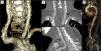

Femoral and left subclavian routes were not suitable for the procedure due to calcified and severe stenoses. Other routes were also rejected, the right subclavian artery due to aortic annulus angulation (>60°) and direct aortic access due to porcelain aorta (Figure 1). The minimum diameter of the left common carotid artery was 6.3 mm, so TAVI was scheduled. Cerebral magnetic resonance angiography was carried out to confirm the presence of collateral perfusion through the circle of Willis.